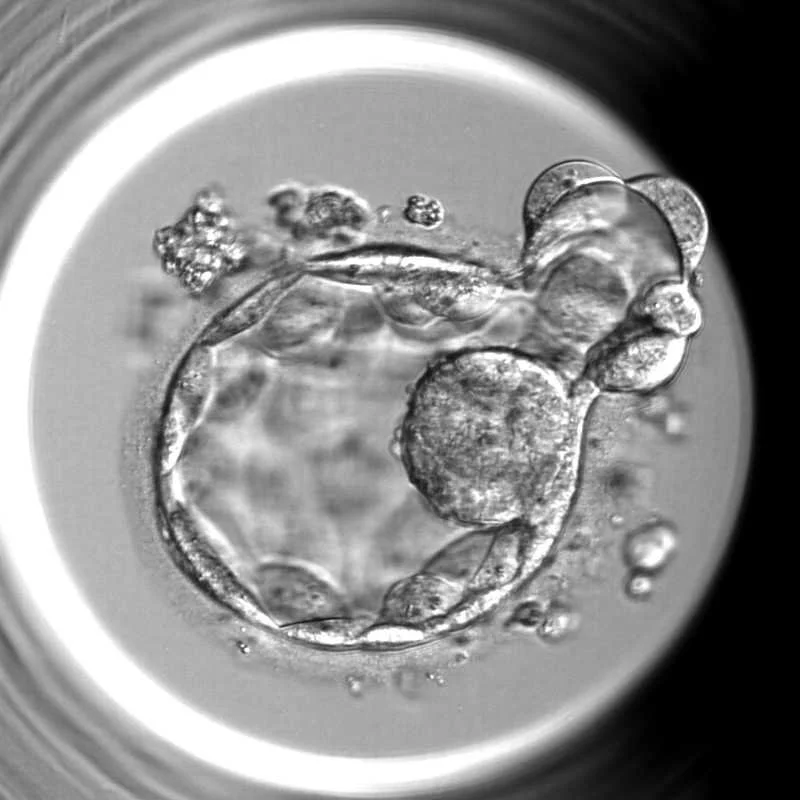

Looking through the top of a glass, exposing the stem cell used for in vitro fertilization.